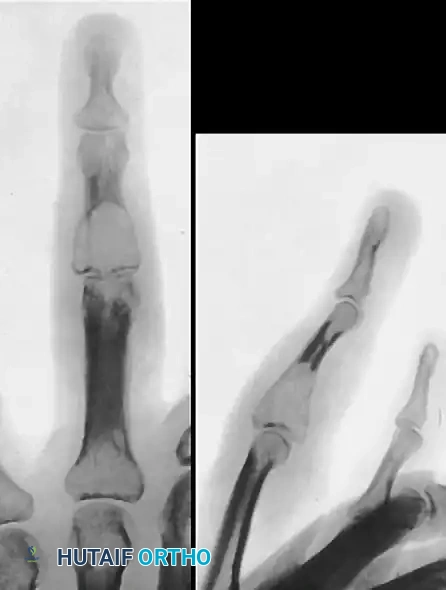

FIGURE 77-17 A, Giant cell tumor of head of fifth metacarpal. B, Pathological fracture caused by tumor.

FIGURE 77-18 Giant cell tumor of middle phalanx. A, Before excision. B, Status 5 years after excision. Tumor has recurred, and proximal phalanx also has become involved. C, After fourth ray was amputated and fifth ray was transposed laterally.